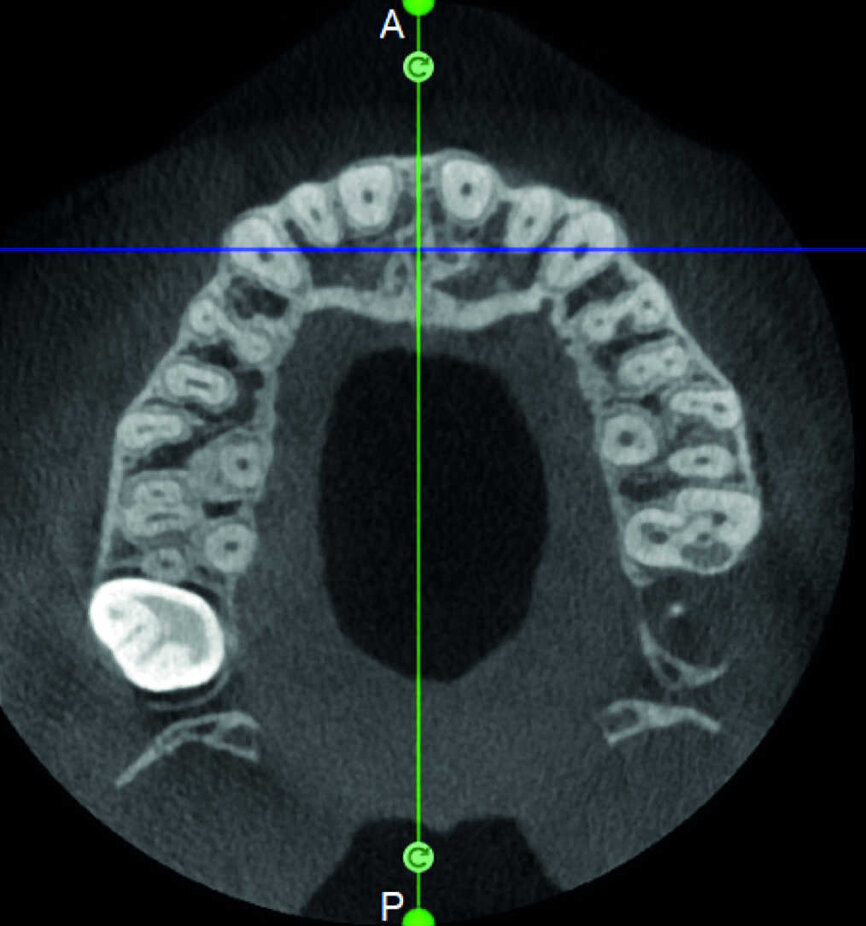

Le cas avec lequel je souhaite commencer mon exposé clinique est un exemple parfait de la difficulté à définir l’origine des symptômes d’un patient, par l’examen d’une simple radiographie intraorale. Non seulement l’examen 2D ne permet pas d’établir avec certitude la présence d’une lésion, mais surtout, il est impossible d’en déterminer la taille, la morphologie et le type. Au contraire, une analyse de l’imagerie 3D offre une image claire de la situation clinique. Chez ce patient, les coupes coronales et sagittales révèlent la présence d’une importante lésion s’étendant de l’apex de la racine mésiale de cette molaire jusqu’à la zone de furcation, tandis que les coupes axiales nous permettent d’analyser précisément l’anatomie endodontique et, en particulier, la forme de la racine mésiale, qui apparaît fusionnée avec la racine palatine. Un panorama complet du cas peut donc guider le processus de décision et orienter le plan de traitement vers une modalité bien précise de traitement (Figs. 1–4).

Indéniablement, l’un des processus pathologiques les plus complexes à traiter est la résorption radiculaire externe invasive, où l’ampleur de la lésion limite les options de traitement. Une évaluation préopératoire de l’emplacement et de l’étendue de la résorption se justifie donc entièrement. Le potentiel de récupération dépend de la planification 3D adéquate de l’intervention, qui ne peut être accomplie qu’après l’examen des clichés CBCT. Il est très important de bien visualiser les coupes de la dent dans les trois plans, et de se concentrer particulièrement sur les coupes axiales, qui s’avèrent stratégiques du point de vue du diagnostic endodontique.